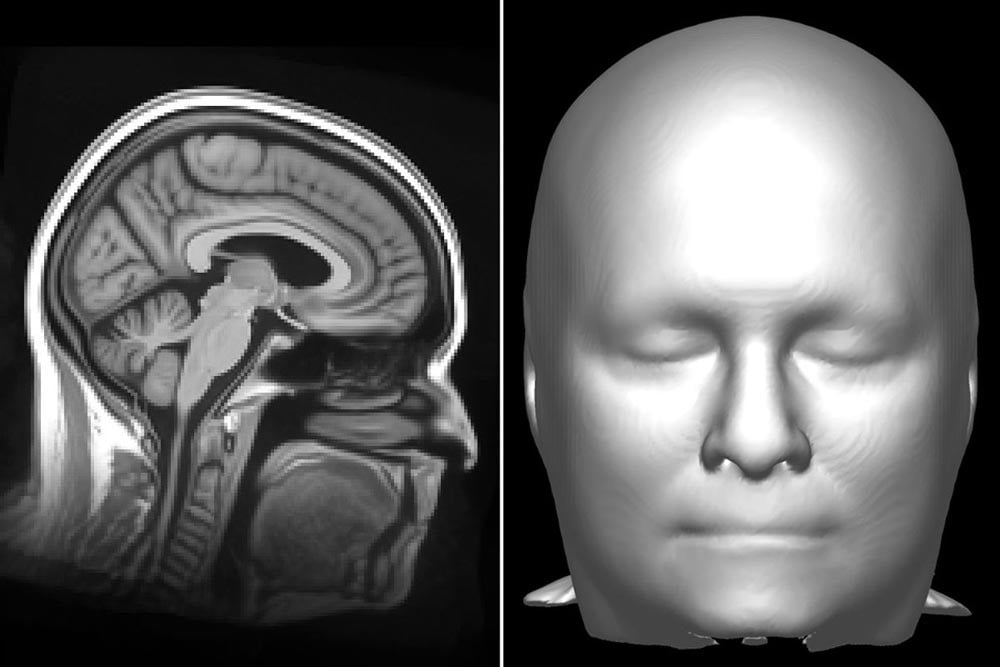

Ein MRT-Scan visualisiert zwar in erster Linie das Innere eines Menschen, bei der Aufnahme werden aber auch die Umrisse des Körpers aufgezeichnet. Bei einer Studie über die Früherkennung der Alzheimer-Krankheit fiel einem Forscher der Mayo Klinik auf, dass man anhand eines MRT-Scans des Gehirns, bei dem die Konturen des Kopfes samt markanter Stellen zu sehen sind, wahrscheinlich eine bekannte Person wiedererkennen kann.

Dieser Gedanke führte zur Studienidee: Könnte eine für Gesichtserkennung trainierte KI Personen anhand von MRT-Scans identifizieren, wenn man zuvor das Gesicht der Person basierend auf dem Scan digital rekonstruiert?

MRT-Rekonstruktion eines Gesichts: Gut genug für die KI-Analyse

Die Antwortet lautet: Ja. Die Mayo-Klinik rekrutierte 84 Freiwillige zwischen 34 und 89 Jahren, von denen ein aktueller MRT-Scan vorlag. Sie wurden aus fünf verschiedenen Perspektiven fotografiert. Zeitgliech rekonstruierten die Forscher das Gesicht der Person digital anhand des MRT-Scans.

Anschließend gaben sie einer Gesichtserkennungssoftware von Microsoft die Aufgabe, die Fotos der Personen mit den aus den MRT-Scans rekonstruierten Gesichtern zusammenzuführen. Die KI konnte 70 der 84 MRT-Scans korrekt dem Foto zuordnen. Für weitere zehn Personen war der passende MRT-Scan zumindest in der Top-5-Auswahl.